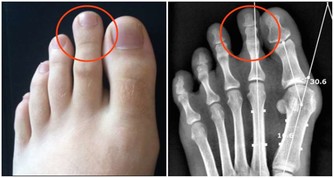

當體液中尿酸濃度超過此值時,將因過剩而在組織中沉積,這種尿酸鹽的結晶沉積在關節滑膜、關節骨、軟骨而導致痛風性關節炎,沉積在皮下則形成痛風石。中西醫均會要求痛風患者不可以攝取高普林食物,然而這些食物可以說是最起碼的美食,要痛風病患完全不吃這些食物,說真的,這種治療的犧牲代價還不小呢!